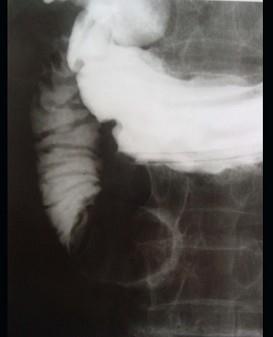

问题 女 ,80岁 ,右上腹疼痛反复发作 6个月,加重 2天 ,曾有胆囊炎及胆结石病史,影像检查如图,应诊断为 ( )

选项 A、十二指肠间质瘤 B、十二指肠腺瘤 C、十二指肠巨大胆结石(胆囊十二指肠瘘) D、十二指肠蛔虫 E、十二指肠息肉

答案 C